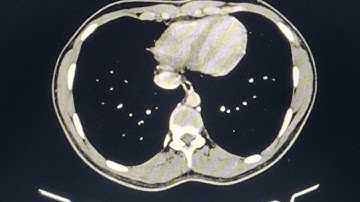

Gastric Duplication Cyst with Cinematic Rendering